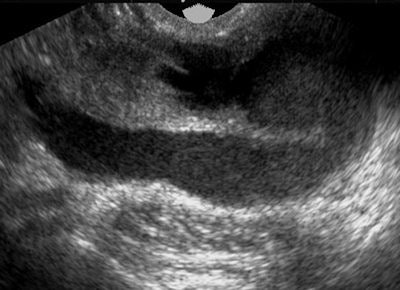

| Endometrioma: Patient presented to the emergency department with lower abdominal pain that became worse during menstruation. Subsequent transvaginal ultrasound demonstrated heterogeneous echotexture. Hypoechoic regions are a result of organizing hemorrhagic debris within hyperechoic septations and wall foci. Anechoic cysts may occur, but they are rare. All images courtesy of Dr. Óran Roche. |